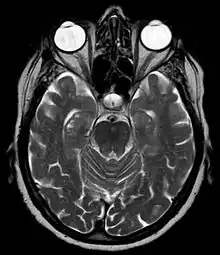

The hippocampal sulcus, also known as the hippocampal fissure, is a sulcus that separates the dentate gyrus from the subiculum and the CA1 field in the hippocampus.

During human fetal development, the hippocampal sulcus first appears at approximately 10 weeks of gestational age. At this stage it exists as a broad shallow fissure along the surface of the dentate gyrus. Gradually, the fissure deepens and shifts toward the cornu ammonis. After about 18 weeks, the walls of the fissure fold into each other and begin to fuse. By 30 weeks, the hippocampal sulcus is normally obliterated except for its most medial part, leaving a shallow surface indentation.[1]

Enlargement of the hippocampal sulcus has been associated with medial temporal lobe atrophy occurring in Alzheimer's disease.[2]